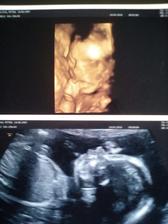

24.3.2016 - 21týden...druhy screning za námi !! čekáme holčičku jupííííí..... váhový odhad 347g a 18cm 🙂 zdrava krásná a naše ♥

31.5.2016 - velky uzv ve 31týdnu (30+1) váha cca 1602g stále holčička uufff 🙂